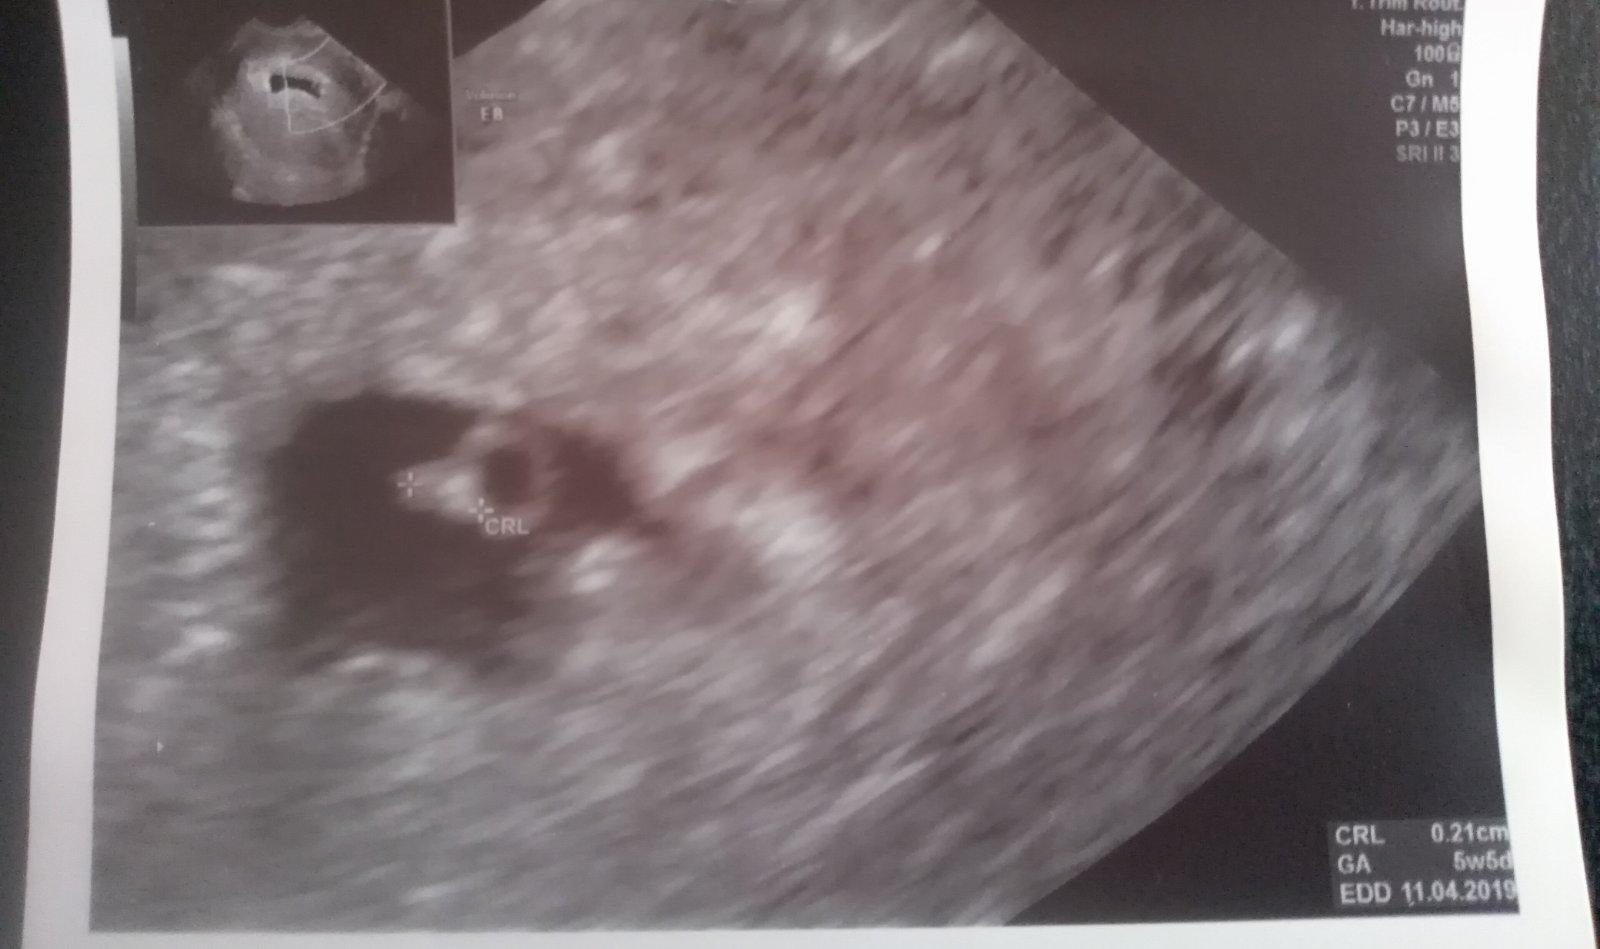

@katka8817 super blahozelam. Ja idem na uzv 24.8.,ak sa mi potvrdia dvojicky,budeme si vymienat skusenosti. V ktorom tyzdni a dni si prosim ta presne bola,ked ti robili tuto snimku ? A to su dutinky alebo uz aj srdiecka ?? Srdiecka ti kedy potvrdili ?

@babikadaska 6+5tt, srdiečka už krásne bili, to bolo včera tá snímka a srdiečka potvrdili v pondelok, to som bola 6+3 tt.

@katka8817 dakujem. Ja sa chystam na prvy uzv ked budem 6tt+5, preto som zvedava co uz moze byt v tomto stadiu vidno 🙂